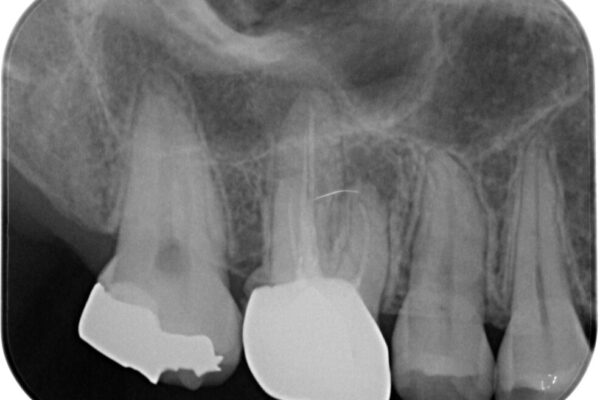

スペースが整った段階で、右下の第一大臼歯と第二大臼歯にインプラントを埋入。

その後、挺出していた右上第一大臼歯と第二大臼歯に装着されていた銀歯についても、審美性と適合性の向上を目的に、オールセラミッククラウンにやり替えました。

これにより、より自然で美しい見た目と、高い精度の咬合が得られています。

• 挺出歯を圧下してスペースを確保!目立たない部分矯正で下顎大臼歯にインプラント治療を実現 治療後画像